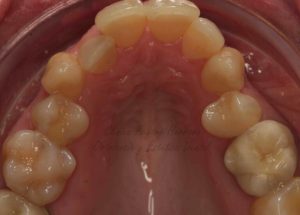

En el momento en el que nosotros le hicimos la exploración clínica vimos que presentaba graves problemas en la salud de su boca. Tal como se puede apreciar en las fotografías que adjunto, el paciente tenía problemas en las encías debido por un lado a la acumulación de placa bacteriana y por otro lado también a que presentaba una maloclusión muy severa. En las fotografías de inicio que le realizamos a este paciente se puede observar cómo presenta mordidas cruzadas en los incisivos y también en los caninos.

Si te fijas en las fotografías que voy a mostrarte las arcadas de la paciente presentaban una forma muy triangular. Los dientes de la paciente no cabían bien a pesar de que ya se había sometido a un tratamiento de ortodoncia con anterioridad en el que se le habían extraído dos premolares superiores y dos premolares inferiores. A pesar de contar con menos piezas dentales, las arcadas eran todavía muy estrechas hecho que provocaba que los dientes no cupiesen y que por consiguiente estuvieran apiñados.